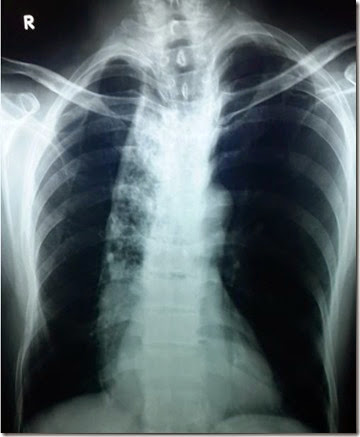

This is a posterior-anterior view of chest on X-ray film. What do you see?

By looking at this X-Ray, you clearly notice an elongated or vertical opacity along the right border of the sternum . If you look below, it disappears behind the right pericardial border. What is this elongated opacity in the mediastinum? Also, the mediastinum is dilated. Moreover, that opacity has shifted the trachea to the opposite side, that is left side. So what is it? Make your differentials in your mind.

Here is the Chest – X-Ray, PA view: